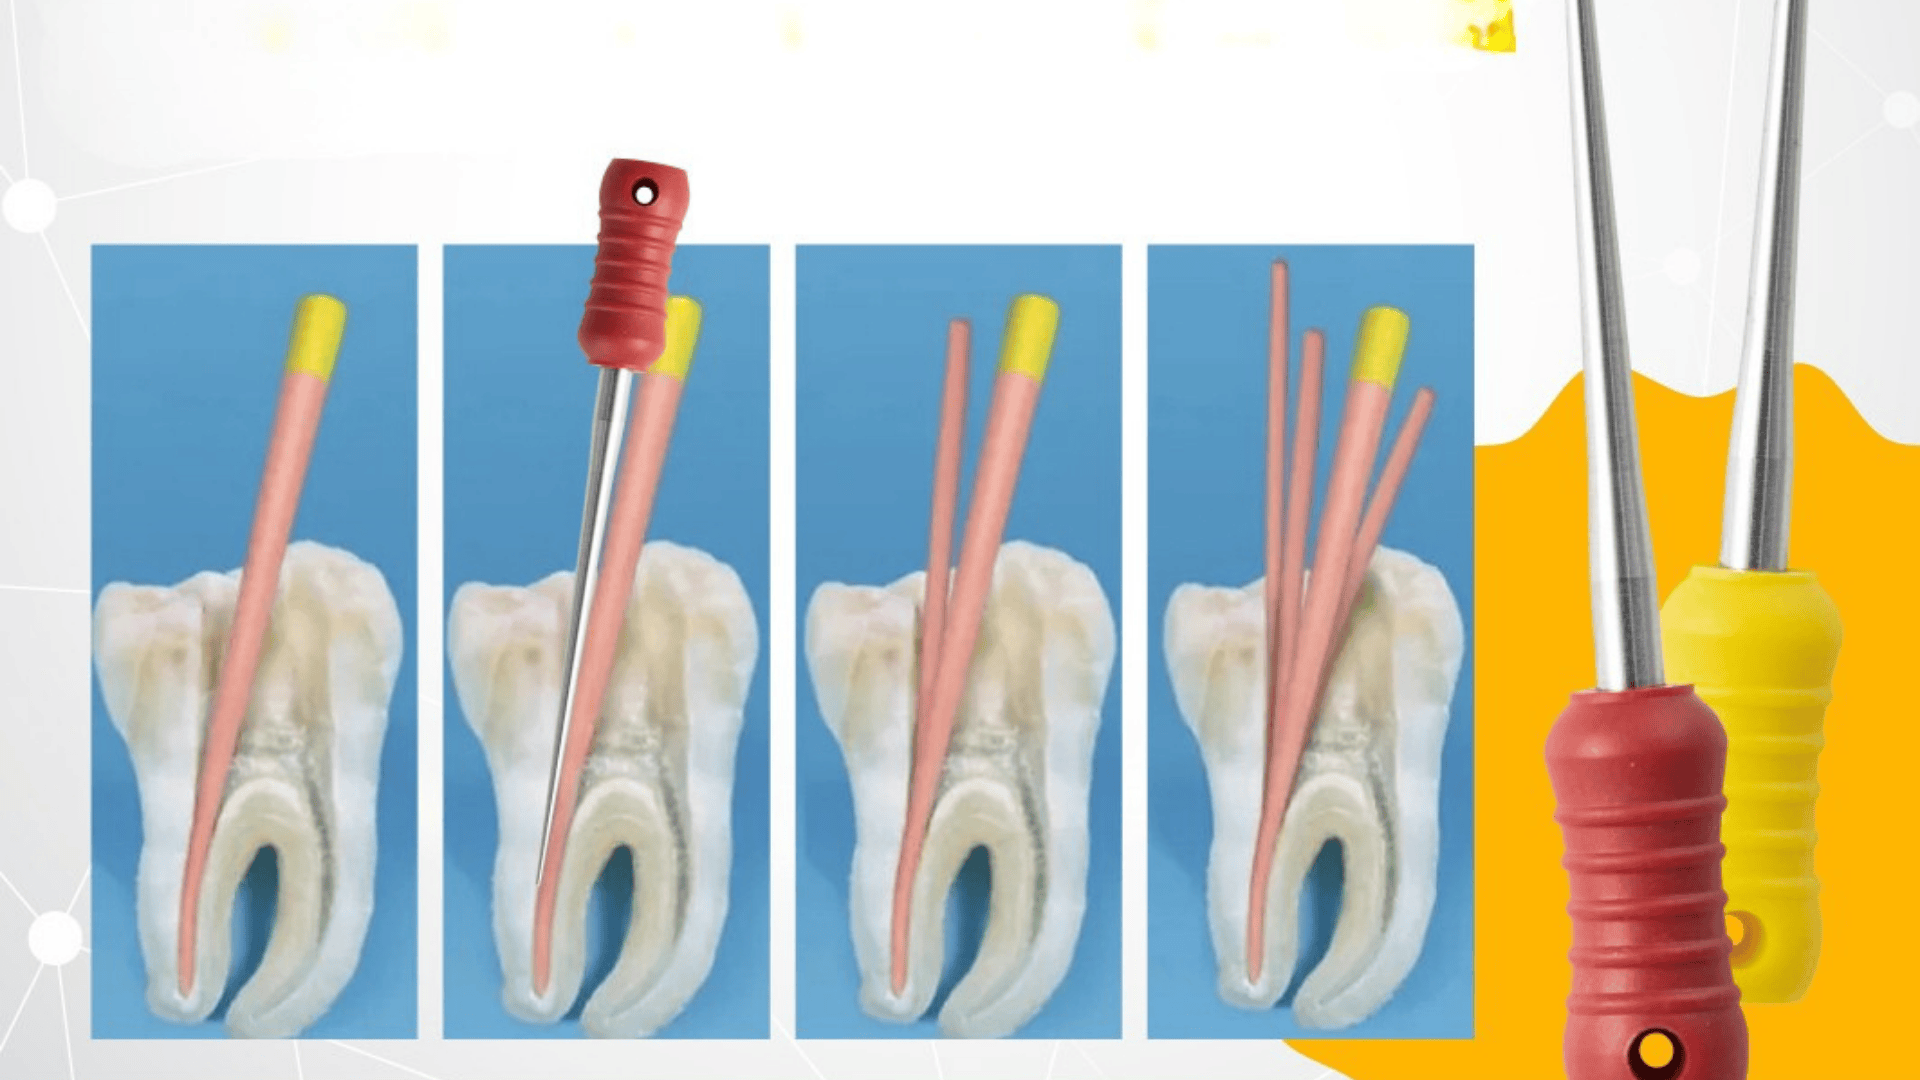

The 5/100 tapered Flare design allows clinicians to apply controlled lateral pressure during obturation, optimizing gutta percha placement without causing canal deformation. The conical tip ensures accurate insertion and guidance within the canal, helping to condense gutta percha efficiently along the canal walls.

The tapered body of the spreader is specifically designed to match accessory-sized gutta percha points, making it ideal for lateral condensation techniques — a widely used method for filling root canals.

The MANI Flare Finger Spreaders are primarily used in the lateral condensation of gutta percha during root canal obturation. Below are some common clinical applications:

After cleaning and shaping, the spreader is used to create space for accessory gutta percha cones alongside the master cone. This ensures dense lateral compaction, reducing voids and improving the seal of the root canal system.

In cases involving premolars or molars, where canal curvature and multiple canals are present, the Flare design allows smoother navigation and placement, minimizing the risk of ledging or transportation.